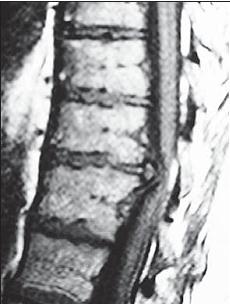

МРТ № 24

На серии снимков МРТ № 24 наблюдаются дорсальные грыжи межпозвонковых дисков в поясничном отделе позвоночника в сегментах Lv—SI Это самый уязвимый межпозвонковый диск, так как в силу своего анатомического расположения на него приходятся самые большие нагрузки. Как говорится, по счёту «последний», а по уязвимости, первый. Поэтому в нём чаще, чем в других межпозвонковых дисках, возникают, различные осложнения, в том числе и грыжи